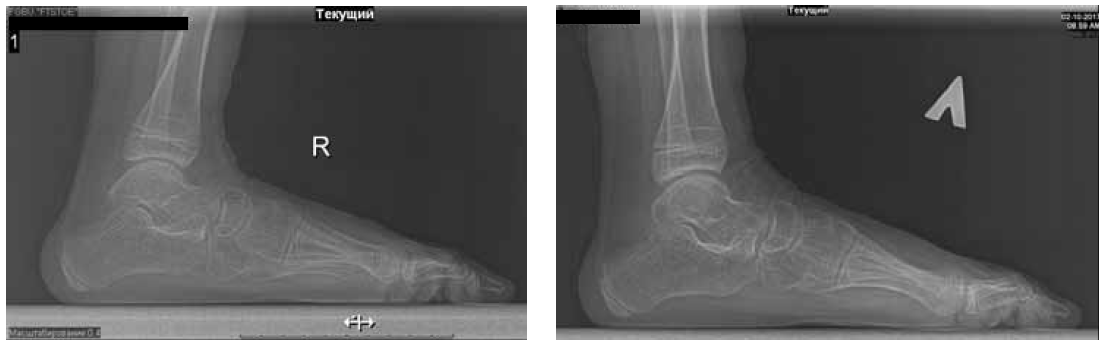

The surgery to eliminate TEPV was performed (Strayer surgery, subtalar arthroereisis, transposition with tenodesis of the anterior tibial muscle tendon under the navicular bone, grafting of the capsule of the talo-navicular joint). A cylinder plaster cast was applied from the upper third of the thigh to the tips of the toes. After 2 weeks, vertical orientation with a partial load in a plaster cast was allowed, 4 weeks after the plaster cast was removed, and a rehabilitation course was started. After 2 years and 6 months, the subtalar implants were removed (Fig. 3, 4).

Fig. 4. Radiographs of the feet under load 1 year after the removal of implants (lateral views)